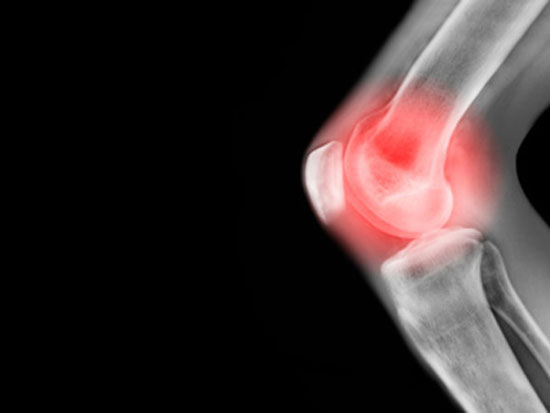

2. 关节过度疲劳和膳食不平衡会导致酸性体质,软骨浸泡在酸性体液中就会降解,滑液的润滑效果也会变差。损失的软骨成分同时存在于软骨和骨骼中,导致骨骼末端变得不平滑并形成骨刺(大的骨骼突起)。由此引起的发炎会限制关节的运动。

原纤维、粘多糖是关节的软骨固体物主要构成。但慢随着年龄的增长人体代谢变,体内氨糖(是构成胶原纤维、粘多糖的小分子前体)合成分泌含量下降,导致软骨合成能力下降,软骨中粘多糖的不足,胶原纤维受损。软骨退化,骨与骨摩擦,诱发骨关节代谢异常与炎症,形成各种关节炎。